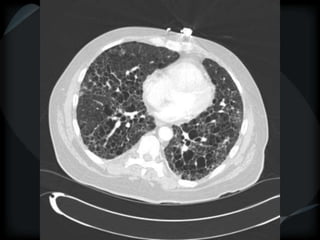

RETICULAR PATTERN - UIP

 peripheral reticular lines / inter and intralobular septae

 honeycomb

 Traction bronchiectasis

 None or minimal ground glass

 Gradient increasing from apex to base

 Skip areas

 Chronic HP = upper and midzones

Chronic HP

Asbestosis